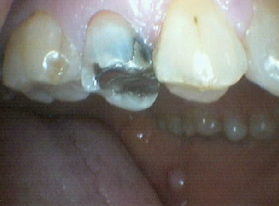

Bruxir Crown, Defective Alloy